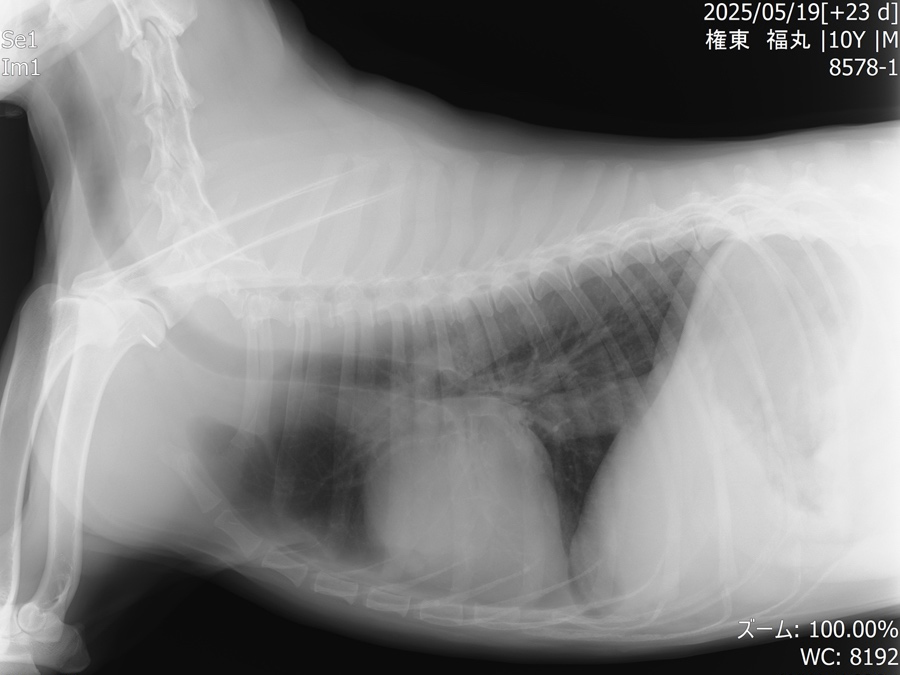

他疾患の手術前検査として実施した胸部レントゲン検査にて、前縦隔部に腫瘤性病変を認めたことから、精査のためCT検査を実施しました。 CT所見より、胸腺腫や異所性甲状腺腫瘍などの腫瘍性疾患が強く疑われたため、胸腔鏡を用いた腫瘤摘出術を行いました。 術前より臨床症状は認められず、全身状態も良好であったため、術後の経過は順調であり、術後2日目に退院となりました。

術後のレントゲン画像写真